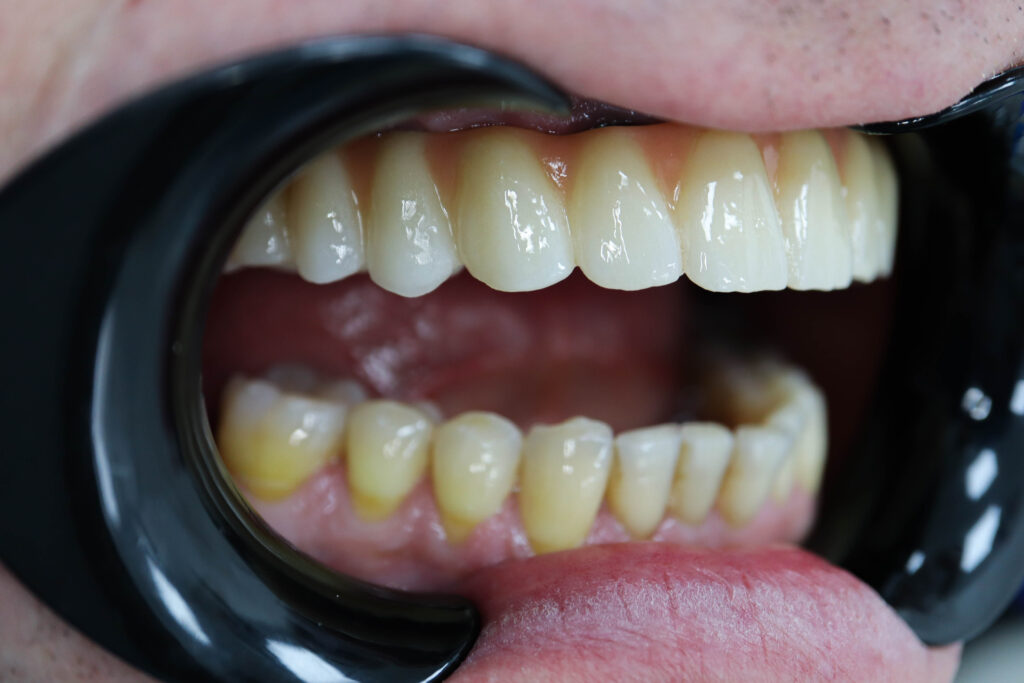

Ситуация до лечения

Пациент продолжает лечение спустя 3 месяца после имплантации и установки временного металлоакрилового протеза с опорой на 6-ти дентальных имплантантах Megagen Anyone.

пациент до имплантации